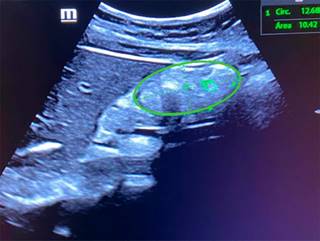

Previo al procedimiento endoscópico, se colocó al paciente en decúbito lateral derecho y se aplicó gel en la región epigástrica, se encendió el equipo de ultrasonido Butterfly iQ/iQ+™ y se seleccionó la configuración predeterminada vista de abdomen, se coloca la sonda universal del mismo equipo de ultrasonido sagitalmente en la región epigástrica, se realizó un barrido en dicha región, inicialmente girando en sentido de las manecillas del reloj y después en contra de ellas, también desplazándose en sentido cefálico y caudal con la finalidad de obtener la vista más adecuada de la región transversal del antro gástrico para realizar una medición de su área transversal abarcando todo el espesor de la pared gástrica (Figura 1), posteriormente de acuerdo a la fórmula de Perlas12 (27.0 + (14.6 × (área transversal del antro gástrico en centímetros)) − (1.28 × edad)) se obtuvo el volumen de contenido gástrico. Este procedimiento fue replicado por dos únicos residentes del servicio de anestesiología, a continuación, se realizó procedimiento endoscópico como previamente había sido planeado por el servicio de gastroenterología aspirando el contenido gástrico total para ser medido. Ambos residentes de anestesiología fueron cegados entre sus mediciones obtenidas y el contenido aspirado por endoscopia, siendo recolectados los datos por un cuarto integrante del grupo de investigación. Para el análisis de datos se utilizó el software Stata versión 14 (StataCorp LLC software, Texas, EE. UU.). Las variables continuas y categóricas se expresaron como medidas de tendencia central. Se obtuvo el índice de κ ponderado para ver el nivel de concordancia entre los resultados medidos entre los usuarios de ultrasonido. Posteriormente se realizó un promedio de los volúmenes obtenidos por ultrasonido entre ambos usuarios, y se obtuvo la correlación por coeficiente de Pearson entre lo medido por ultrasonido promedio y lo aspirado por endoscopia, así como lo medido por ultrasonido promedio y las horas de ayuno, y por último la medición de contenido gástrico y las horas de ayuno. El criterio de significación estadística fue p < 0.05.